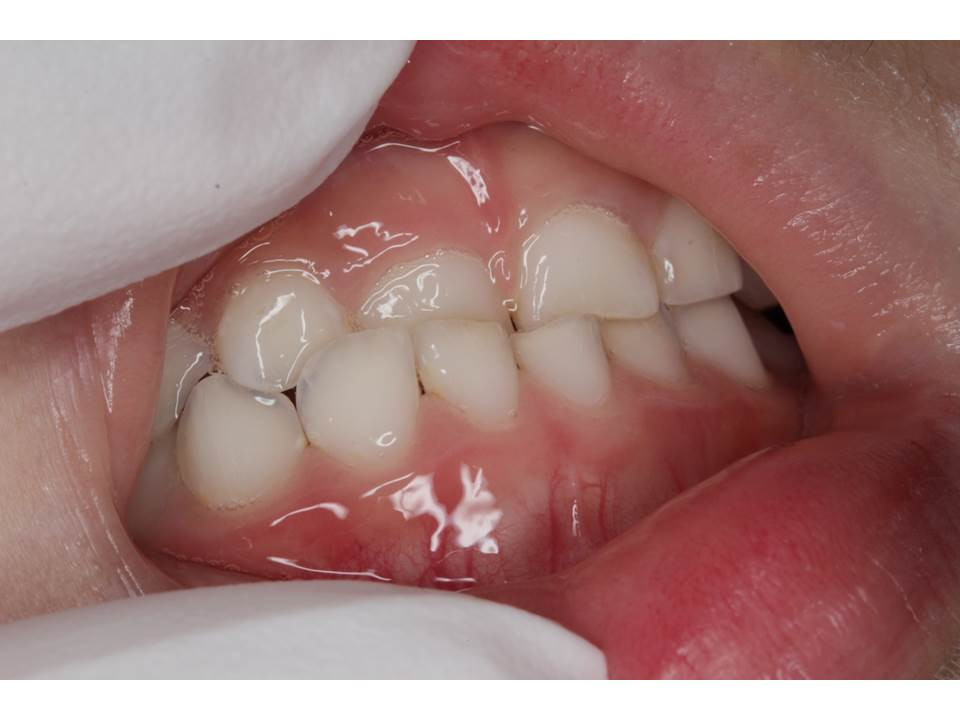

上の前歯が下の前歯より内側に位置し、逆になっている場合には「反対咬合」と言います。上の前歯と下の前歯が交叉している場合には「交叉咬合」と言います。親御さんから見ても、見た目から簡単にわかります。画像は、当院に受診された幼児で、3本の上の前歯が下の前歯に隠れてしまう交叉咬合の状態でした。